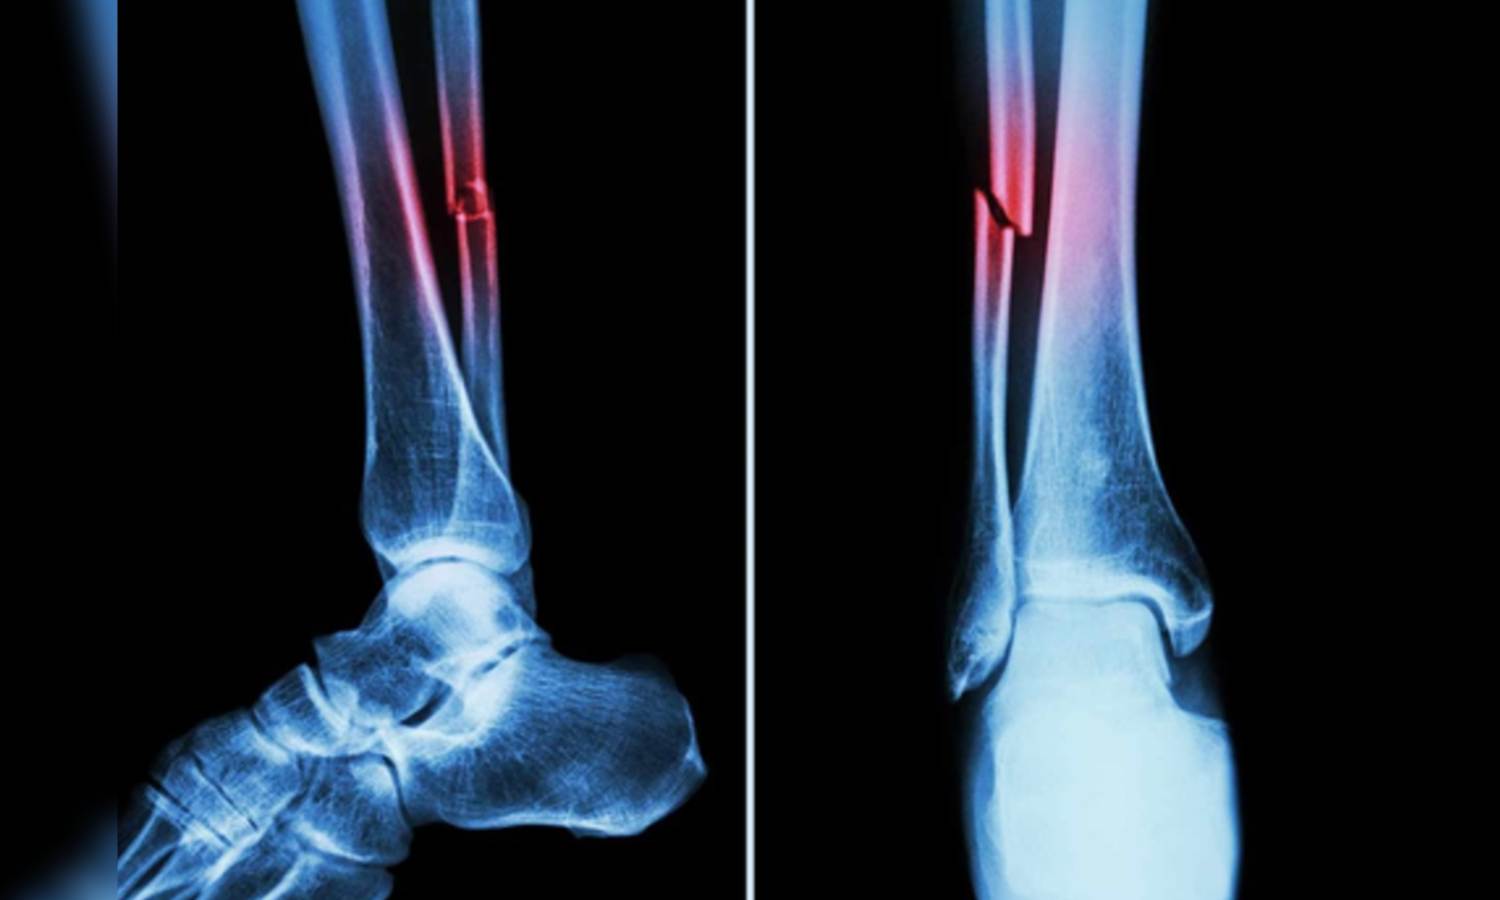

Representative Image (IANS)